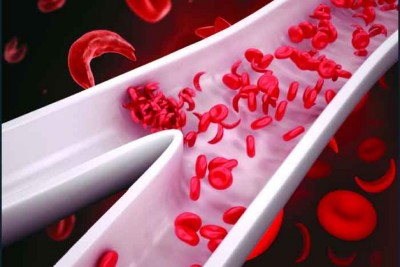

في «عالمي الأنيميا المنجلية».. 7 مضاعفات و«فحص الزواج» ضرورة للوقاية

يحتفي العالم، في 19 من يونيو كل عام، باليوم العالمي للأنيميا المنجلية، بهدف التعرف إلى فقر الدم المنجلي وطرق الوقاية منه والتعامل الصحيح معه. وتُعرف وزارة الصحة السعودية فقر الدم المنجلي بأنه مرض ينتج فيه الجسم خلايا دم حمراء غير طبيعية الشكل مثل الهلال أو المنجل، وهي مجموعة من اضطرابات خلايا الدم الحمراء الموروثة. فقر الدم المنجلي نوع وراثي ينتقل عن طريق الجينات من الآباء إلى أطفالهم، أي إنه ليس مُعديًا ولا... |